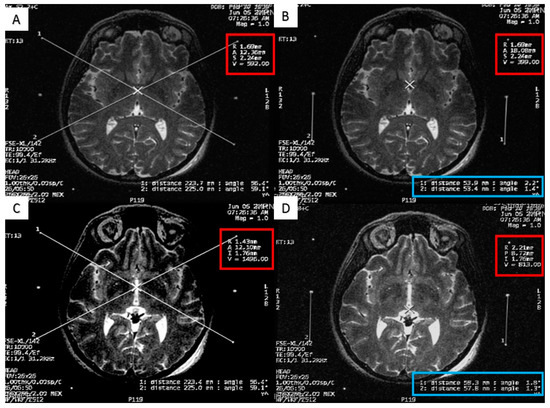

Figure 4.

Calculating the subthalamic nucleus (STN) coordinates from the magnetic resonance imaging (MRI) console. (A) two diagonal lines intersecting at the center of the frame at the STN level with MRI coordinates of the center of the frame shown inside the red square; (B) a crosshair at the center of the left STN, with its MRI coordinates shown inside the red square, two line are drawn between the middle and lower fiducials on both sides of the frame and their lengths (in the blue rectangle) are used to calculate the Z coordinate; (C) a crosshair at the center of the right STN, with its MRI coordinates shown inside the red square, two line are drawn between the middle and lower fiducials on both sides of the frame and their lengths (in the blue rectangle) are used to calculate the Z coordinate.

In the operation room, we used the FrameLink software, which is a part of StealthStation navigation system (Medtronic, Minneapolis, MN, USA) to confirm our calculations of the direct STN coordinates (Figure 5). This software compensates for head and frame tilt in any direction. The final coordinates for the procedure were derived from the two techniques, and subsequently adjusted using intraoperative electrical microrecording and macrostimulation.